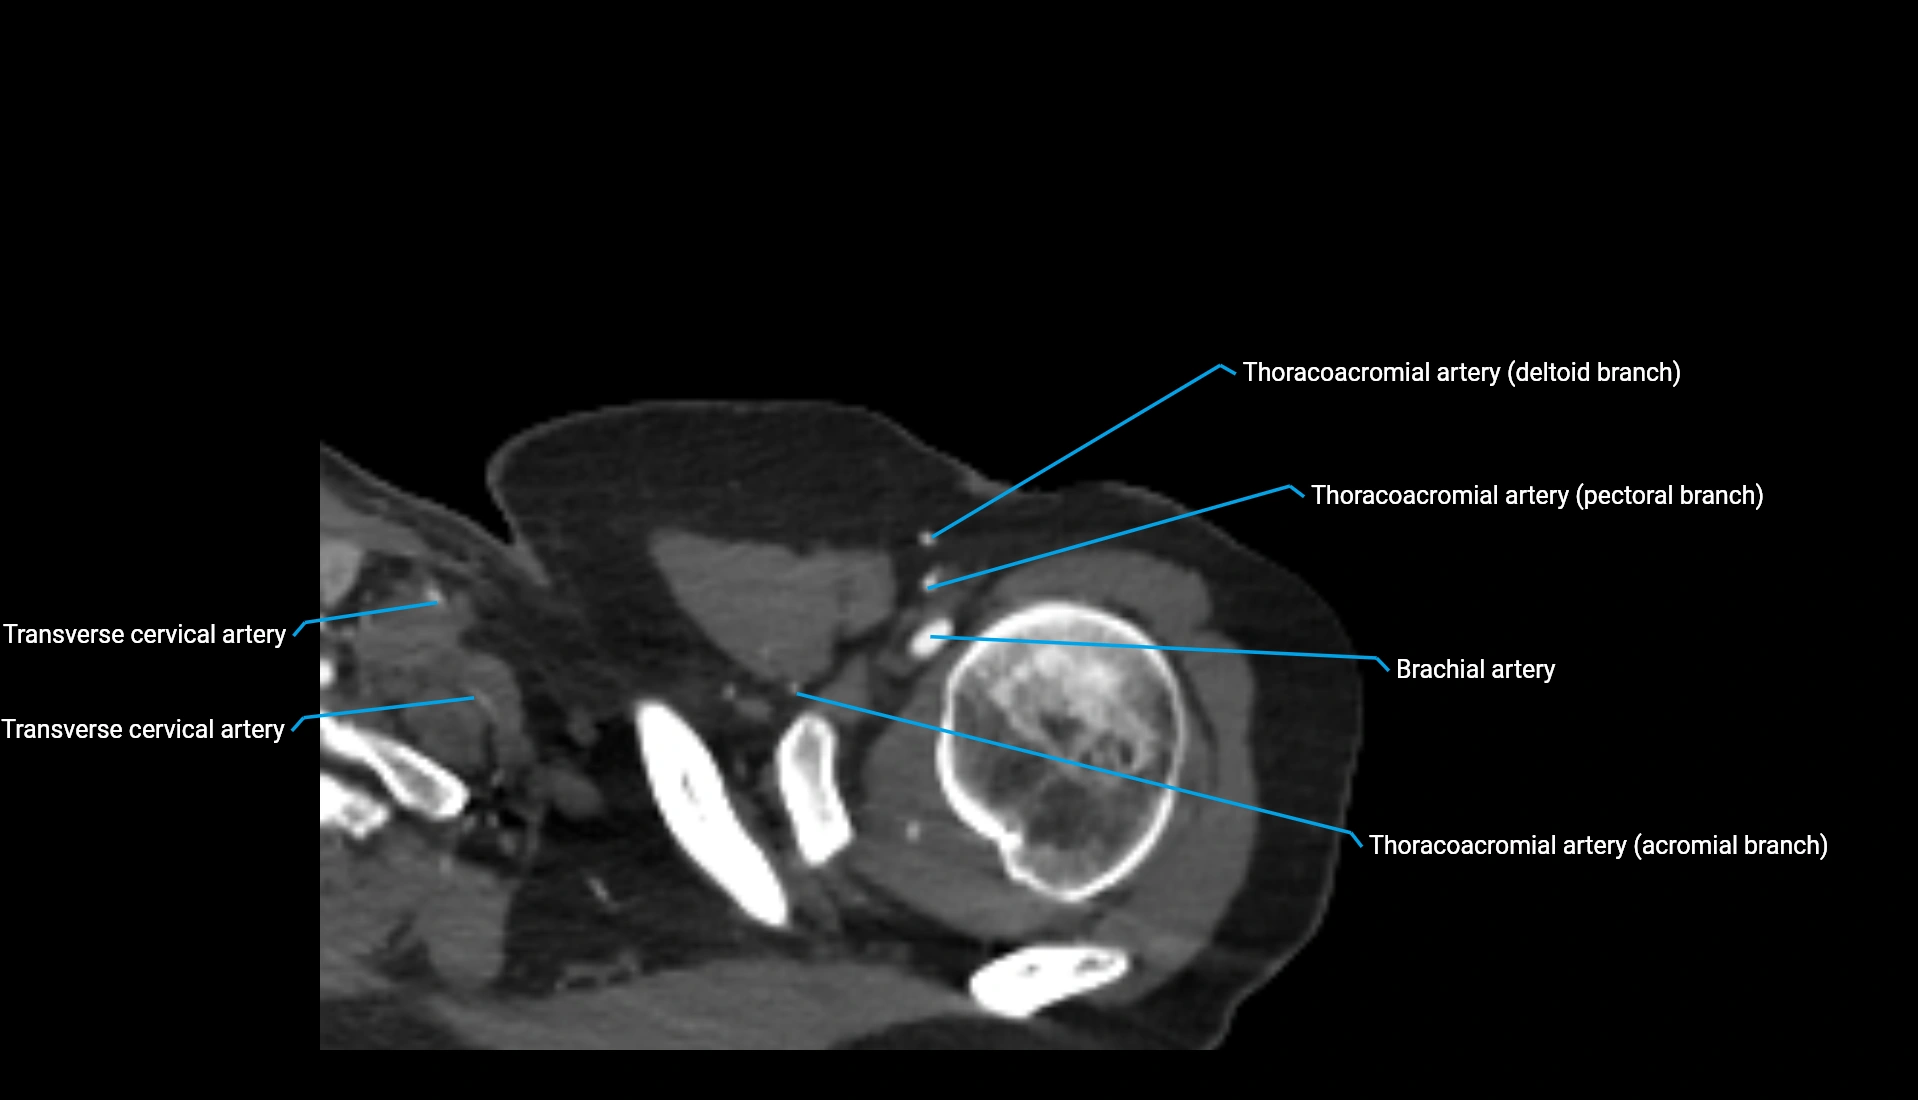

CT Appearance

Non-Contrast CT:

• Cortex: High-density, sharply defined

• Subchondral bone: Dense cancellous matrix

• Articular surface: Smooth concave contour articulating with the capitellum

• Excellent for evaluating bone integrity, alignment, and subtle fractures